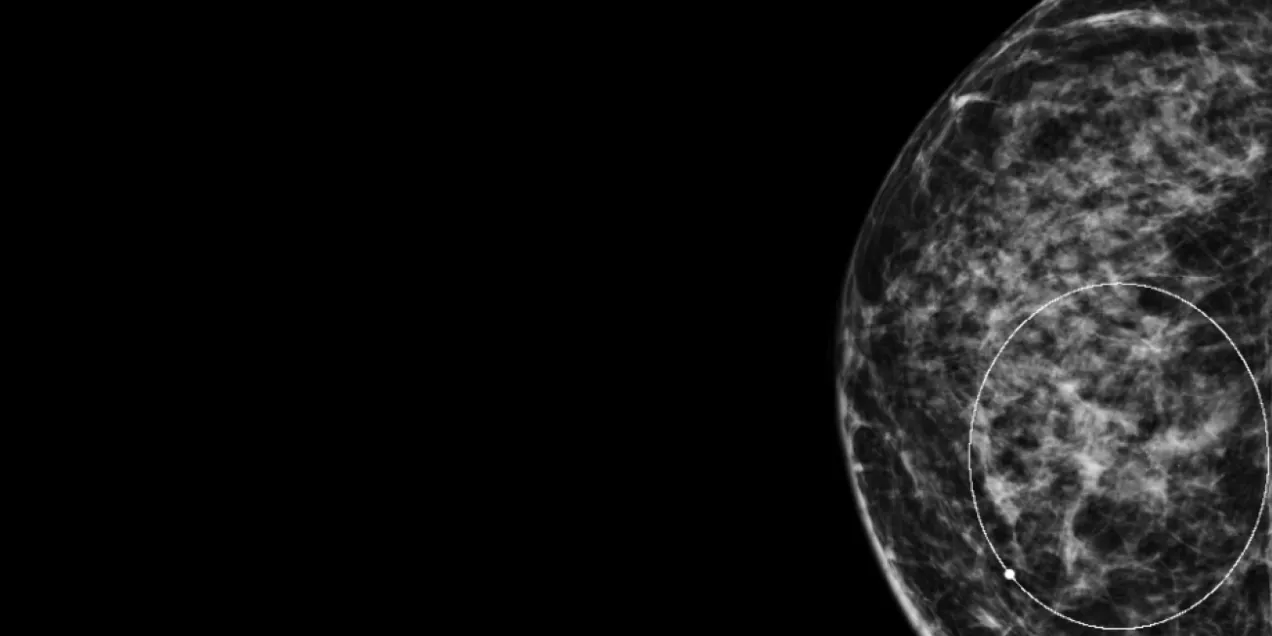

Mammogram image of the right breast showing dense breast tissue with a circular marking highlighting an area of interest.

Today, most radiology practices in the U.S. now use digital mammography because, compared to analog film, it provides better quality images with improved tissue contrast. Studies have shown that digital mammography is particularly better than film mammography for dense breasts, as well as for younger patients, who tend to have denser breast than older patients. Digital mammography also has the added benefit of lower radiation dose compared to traditional analog mammography.

Looking forward, digital breast tomosynthesis (DBT) is a promising new technology that acquires multiple low-dose mammographic projections through the breast. DBT has been shown to reduce false-positive findings and improve the detection rate of invasive cancers. Hence, DBT has been called “a better mammogram” and just may become the standard for mammographic screening once more vendors obtain the propped approvals to offer the technology.